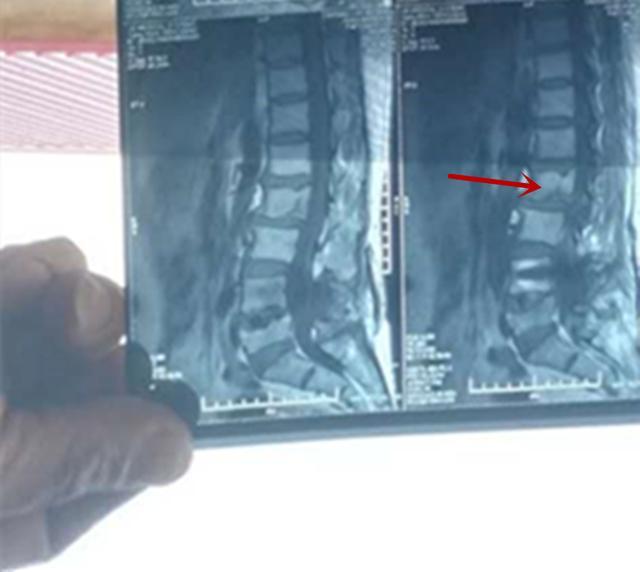

我告诉她必须做一个核磁共振的检查,虽然有钉子,但是目前的钉子都是钛合金,低磁场的核磁共振是可以做的。于是,就有了下面的核磁片子:

一看这片子,我再次想教育教育小姨子,片子放反了不说,还这么小,刚拿起电话,可心中胆怯,把电话放下,默默地接受了现实,凑合看吧,实在看不清楚再说。于是,选出了我需要看的地方:

第二腰椎在核磁共振上是有异常信号的,大概率考虑骨折,当然,从专业角度来说,还需要其他信号的支持,不过,当地医院的报告显示:腰2椎体骨折。怪不得小姨子的阿姨腰那么痛了,是因为这个骨折。

这下问题解决了,诊断明确,和肇事方就没有那么多扯不清的事情了。这件事告诉我们:某些情况,患者临床症状很重,当X线无异常时,做核磁共振检查是很有必要的。小姨子对我表示感谢,发了三朵玫瑰花,这件事我要跟老婆说吗?(哈哈哈)